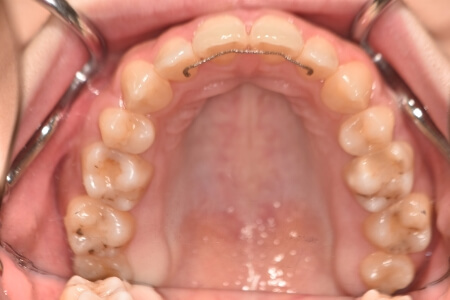

開咬(抜歯)【2245】

初診時

症例 症例 症例 症例

治療内容の詳細 初診時18歳の女性で、前歯がでている事を気にされ来院されました。

検査の結果、開咬を伴うアングルⅡ級1類不正咬合と診断しました。

治療としては、上顎第一小臼歯を抜歯の上、セルフライゲーションブラケット装置(デーモンシステム)とマウスピース型矯正装置(インビザライン)で配列を行いました。顎間ゴムの協力もあり、開咬がきれいに改善されました。

この際、上顎に歯科矯正用アンカースクリューを設置し上顎前歯部後退時の土台としました。